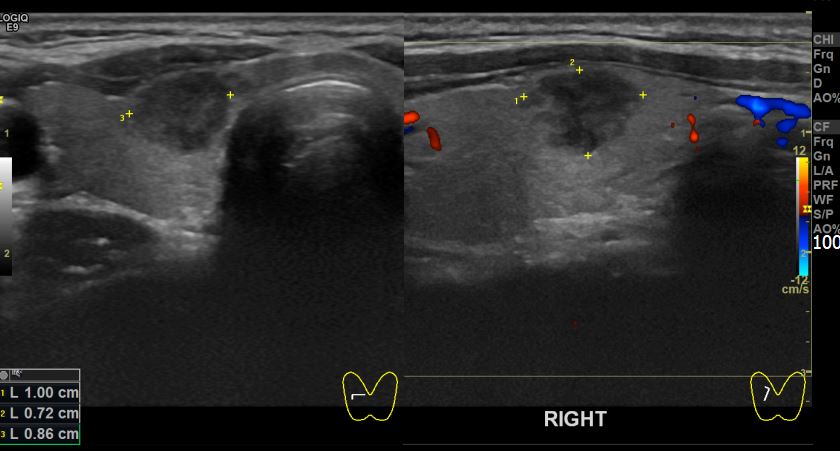

상기환자 건강검진상 이상소견 내원하신 30대중반 여성분으로 우엽 의심스러운혹 세포검사진행후 갑상선암으로 진단되었습니다